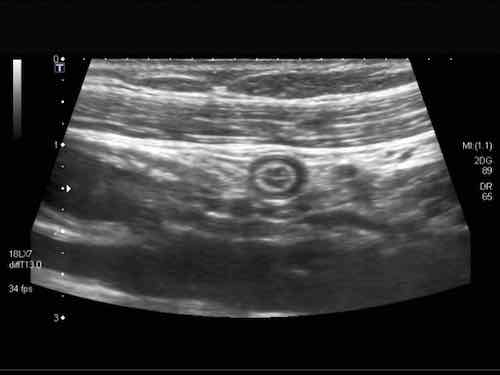

Intussusception

Đây là hình ảnh siêu âm của một trẻ 2 tuổi bị lồng ruột hồi manh tràng từng đợt, được khám trong khoảng thời gian giữa các cơn.

Hồi tràng với nhiều mảng Peyer sa vào manh tràng.

Hình ảnh siêu âm kinh điển của lồng ruột hồi-manh tràng ở hai trẻ khác nhau.

Trong cả hai trường hợp, đoạn hồi tràng bị lồng được định vị không đối xứng bên trong ống lồng ngoài, do mạc treo ruột tăng âm có chứa mỡ, bám vào hồi tràng và đi theo hồi tràng khi bị kéo vào trong.

Trong mạc treo, siêu âm cho thấy một hạch bạch huyết mạc treo (hbh) phóng đại ở cả hai.

Các hạch này phì đại như một phần của tình trạng tăng sản hạch bạch huyết toàn thân và khônghu trú trong lòng hồi tràng.

Do đó đây không phải là điểm dẫn đầu nguyên phát. Ở bệnh nhân bên phải, ruột thừa (mũi tên) cũng bị kéo vào trong.

Lưu ý cấu trúc đa lớp của thành bụng phía trước của phức hợp lồng ruột, đại diện cho ba lớp thành ruột bị gấp lại.